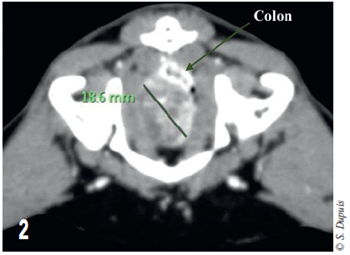

Cette masse déplace le côlon dorsalement à gauche. Elle se trouve à 18 mm de la vessie dorsalement à la symphyse pubienne (figure 2).

Photo 2 – Coupe transversale tomodensitométrique de l’abdomen. Le côlon est déplacé et écrasé dorsalement à la masse